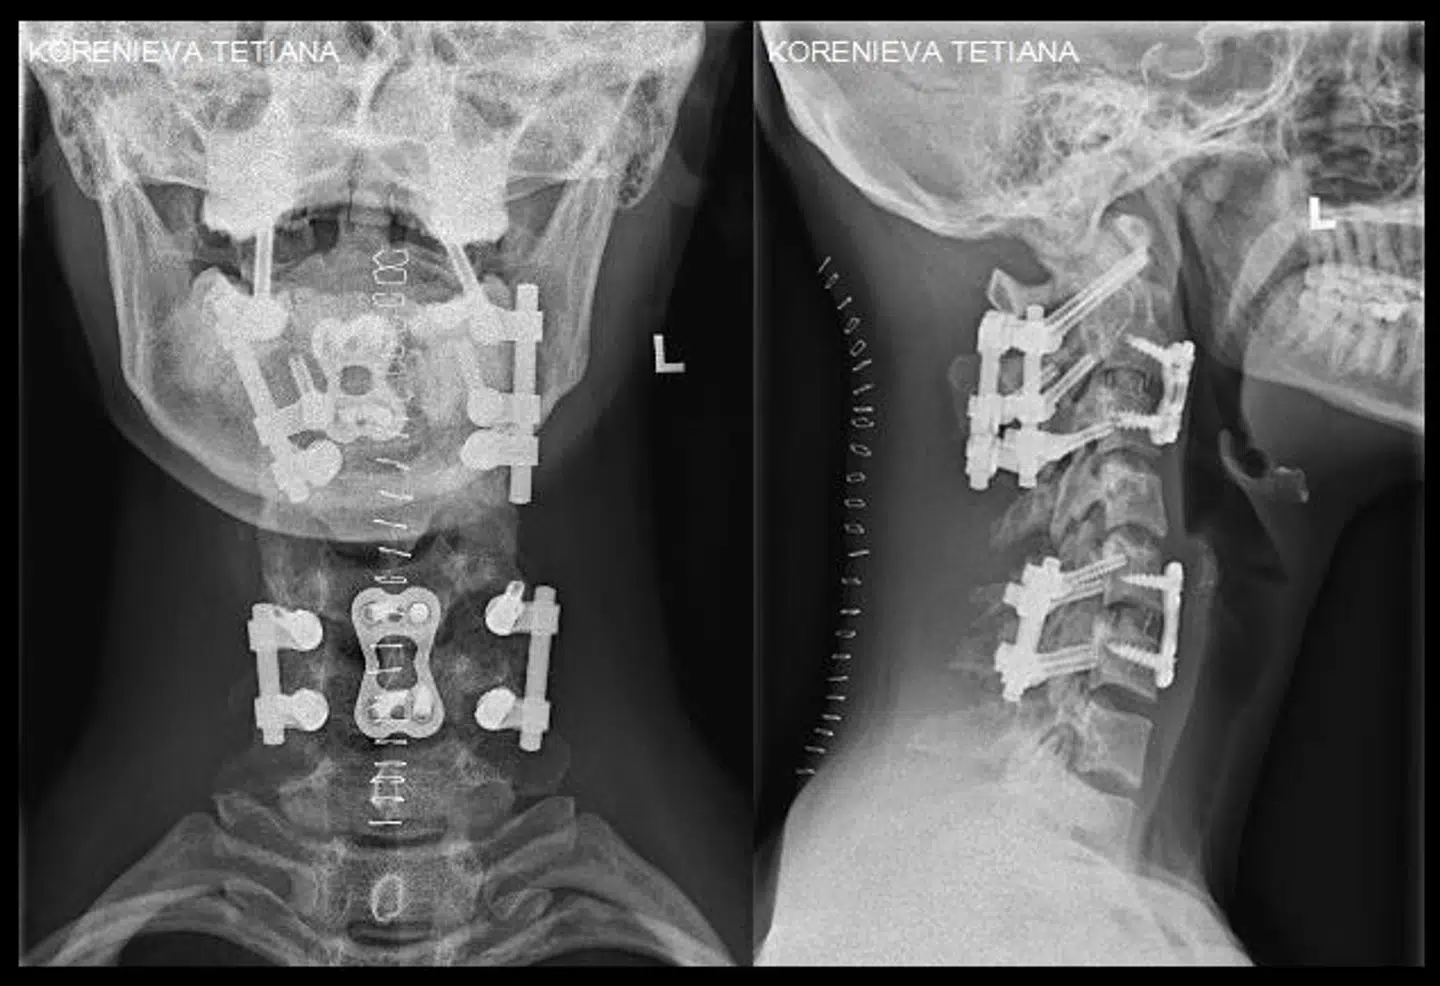

Læger på et sygehus i Hamburg har indopereret 18 skruer, fire metalstænger og to metalplader i nakken på Tetiana Korenieva.

»Næsten alle knogler i hendes nakke har fået kirurgisk behandling,« skriver han.

Men operationen har også negative følger. På grund af alle metal-delene er Tetiana ikke længere i stand til at bevæge hovedet.

»Hendes hoved er nu for evigt blokkeret af implantater,« skriver Sebastian Hofmann.